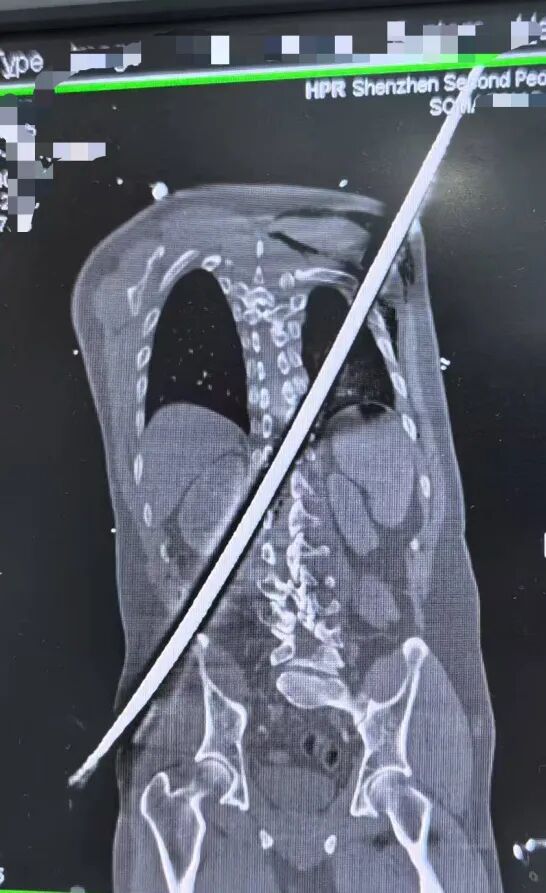

据了解,一场工地意外让男子遭遇了致命重创。一根粗壮的钢筋,以67厘米的长度,从他右侧臀部刺入,斜穿躯干,最终从左后侧肩背穿出。

被紧急送到深圳二院时,患者已经陷入休克,生命体征微弱,随时可能离世。CT检查更让医护人员倒吸一口凉气:钢筋紧贴大血管、肾脏,击穿脊柱椎管,患者双下肢无法活动,稍有晃动就可能引发瞬间大出血。

专家团队根据CT影像精准判断:钢筋穿行路径极度凶险,如同在体内“走钢丝”,手术必须快、准、稳,一旦失误就是致命风险。医院当即决定:立即手术,全力一搏。